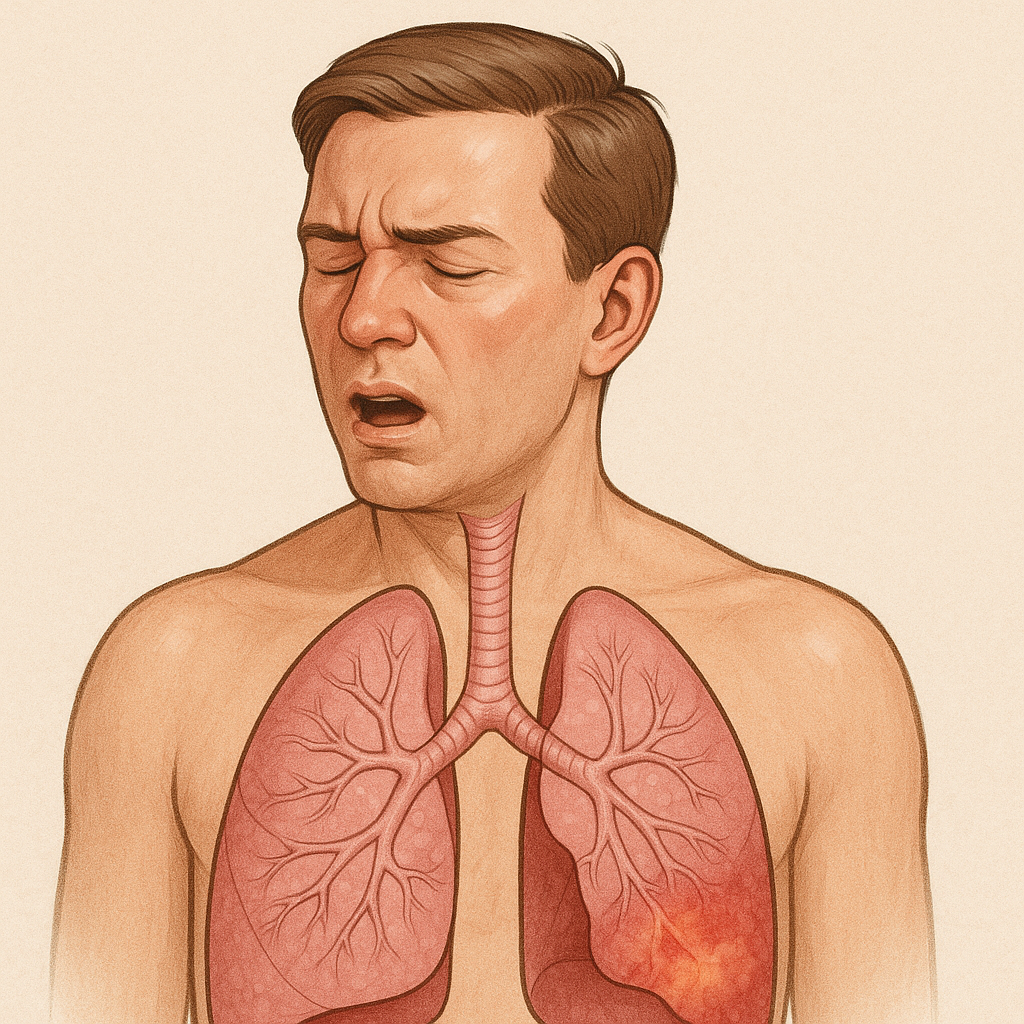

# Respiratory

Chronic Obstructive Pulmonary Disease (COPD)

क्रोनिक ऑब्स्ट्रक्टिव पल्मोनरी रोग (सीओपीडी)